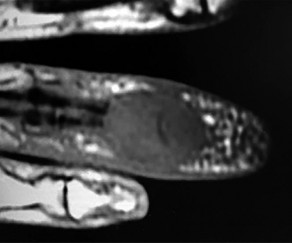

Figures 31a through 31d are the radiographs and MR images of a 52-year-old man who has a 7-week history of right ring finger pain, redness, and swelling. He accidentally stuck his finger with a toothpick 1 week before developing symptoms. There is purulent drainage from the puncture wound site. He was treated with oral antibiotics for 10 days and intravenous (IV) antibiotics for 3 weeks before being seen. Initial cultures grew _Eikenella corrodens_. What is/are the best next step(s)?

This patient had a septic DIP joint that was treated with antibiotics alone. As a result, he developed osteomyelitis with bone destruction and an abscess. The correct answer is debridement of both bone and soft tissue with abscess drainage. Antibiotic treatment without surgery would not successfully eliminate this infection. A bone scan and biopsy are not appropriate because this problem is an infection and not a tumor, and the MR imaging provided enough diagnostic information. Amputation is not indicated prior to an attempt to salvage the digit. Amputation through the DIP joint would not remove the infected bone in the middle phalanx and would provide an inadequate level of resection.